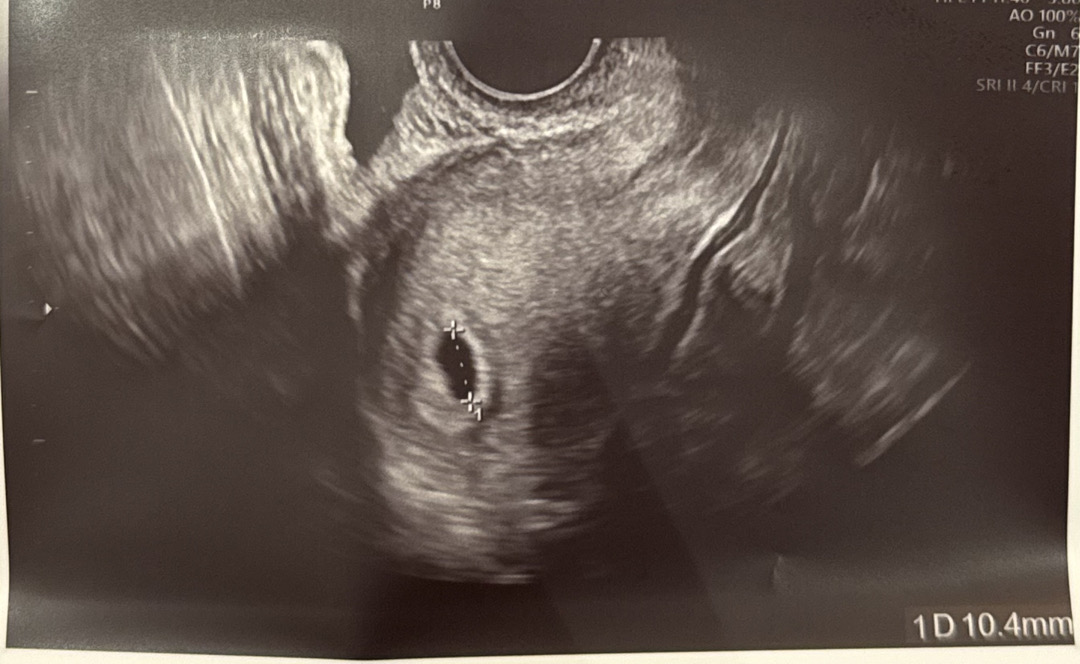

6주3일 초음파 봐주세요ㅠ

오늘 초음파를 찍고왔는데 6주차에는 보통 난황이 보인다고 하던데 저는 아기집만 보이는것같은데ㅠㅠ 이런분들 혹시 있나요?? 5주차때 아기집이 0.34cm 였고 오늘 봤을때 1.04cm로 커지기는 했어요...

좀더 커서 아기가 보이고 난황이 보이면 그때 다시 몇주차인지 확정되고 임신확인서 받으실 거예요. 지금 주수는 엄마 배란추정일로 계산한거라 정확하지 않아요! 천천히 기다려보세요 좋은소식 기다릴게요~^^

이 사진만 봤을 땐 난황은 안 보이네요 아기마다 자라는 속도가 다르고 자연임신은 원래 더 늦게 보이기도 하니까 좀 더 기다려보세요

6주면 난황 보이는게 정상이긴해요... 조금더 기다려보세요! 애기가 자라고 있는걸수도있어요